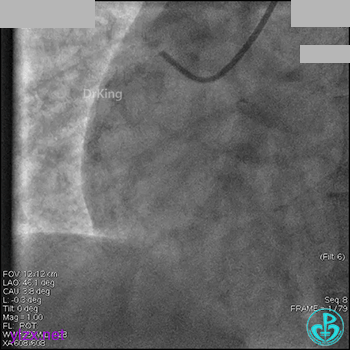

右冠脉中段充分扩张后欲植入3.5×38mm支架时,支架难以通过中远段扭曲处,且指引导管、导丝弹出飞扬。反复尝试导丝重新到达右冠脉远端时通过不顺利,局部造影剂滞留,远端血流接近3级。